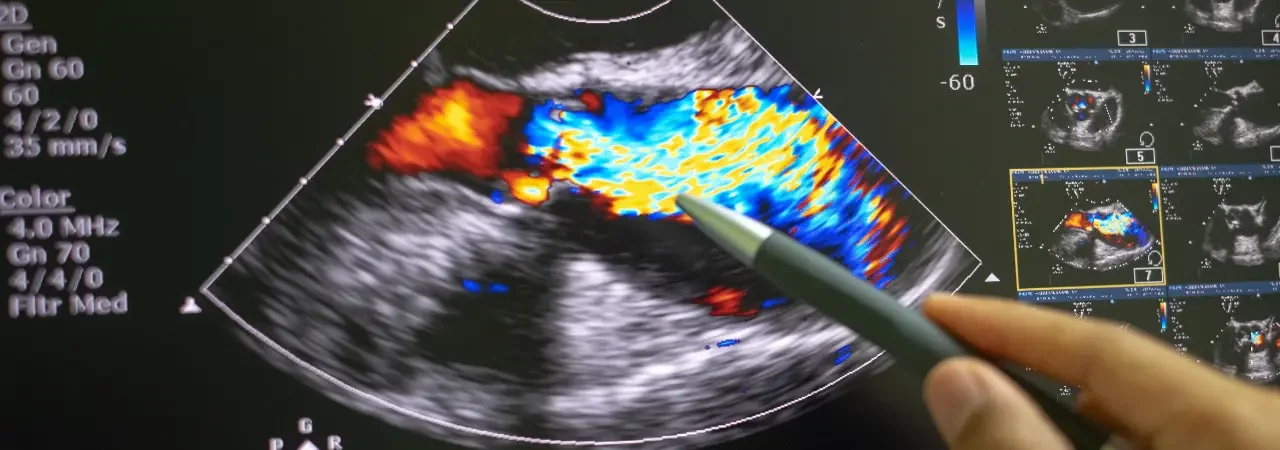

Ekokardiyografi | Kalp ve Kapak Yapılarının Ayrıntılı İncelenmesi

Ekokardiyografi türlerini, TTE ve TEE hazırlığını, uygulama adımlarını, kapak hastalıklarının değerlendirme kriterlerini ve sık yapılan...